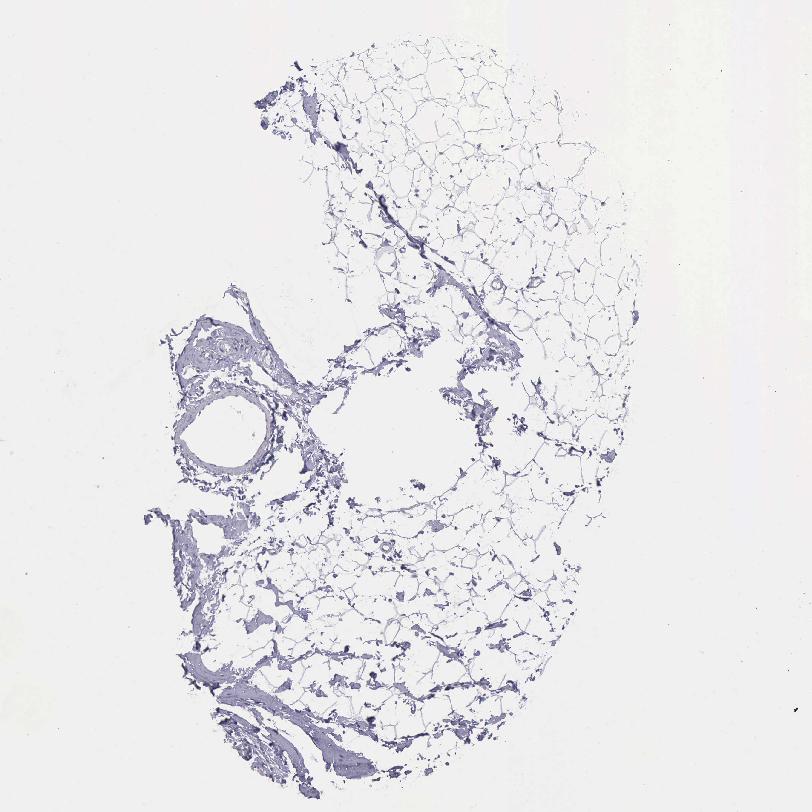

TISSUE PRIMARY DATA BREAST Show tissue menu

Breast

BREAST - Antibody stainingi

Antibody staining in the annotated cell types in the current human tissue is reported as not detected, low, medium, or high, based on conventional immunohistochemistry profiling in selected tissues. This score is based on the combination of the staining intensity and fraction of stained cells.

Each image is clickable and will lead to virtual microscopy that enables deeper exploration of all samples and also displays staining intensity scores, fraction scores and subcellular localization as well as patient and tissue information for each sample.

Antibody HPA001056Antibody CAB005081

Adipocytes Not detectedLow

Glandular cells Not detectedNot detected

Myoepithelial cells Not detectedNot detected